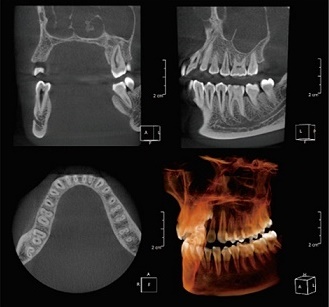

精密検査

インプラントの治療が決まったら、骨やかみ合わせの具合などの検査をいたします。

検査方法は歯科用CT検査と歯周病検査、歯の型を取って模型診査などをいたします。

検査結果によってはインプラント治療が不可能な場合もあります。